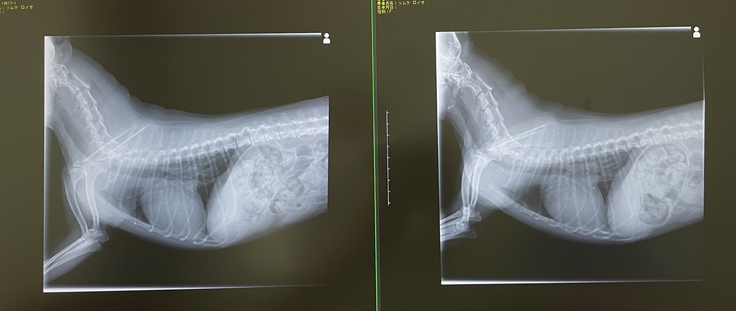

左:2021年12月 右:2021年7月

左:2022年6月 右:2022年4月